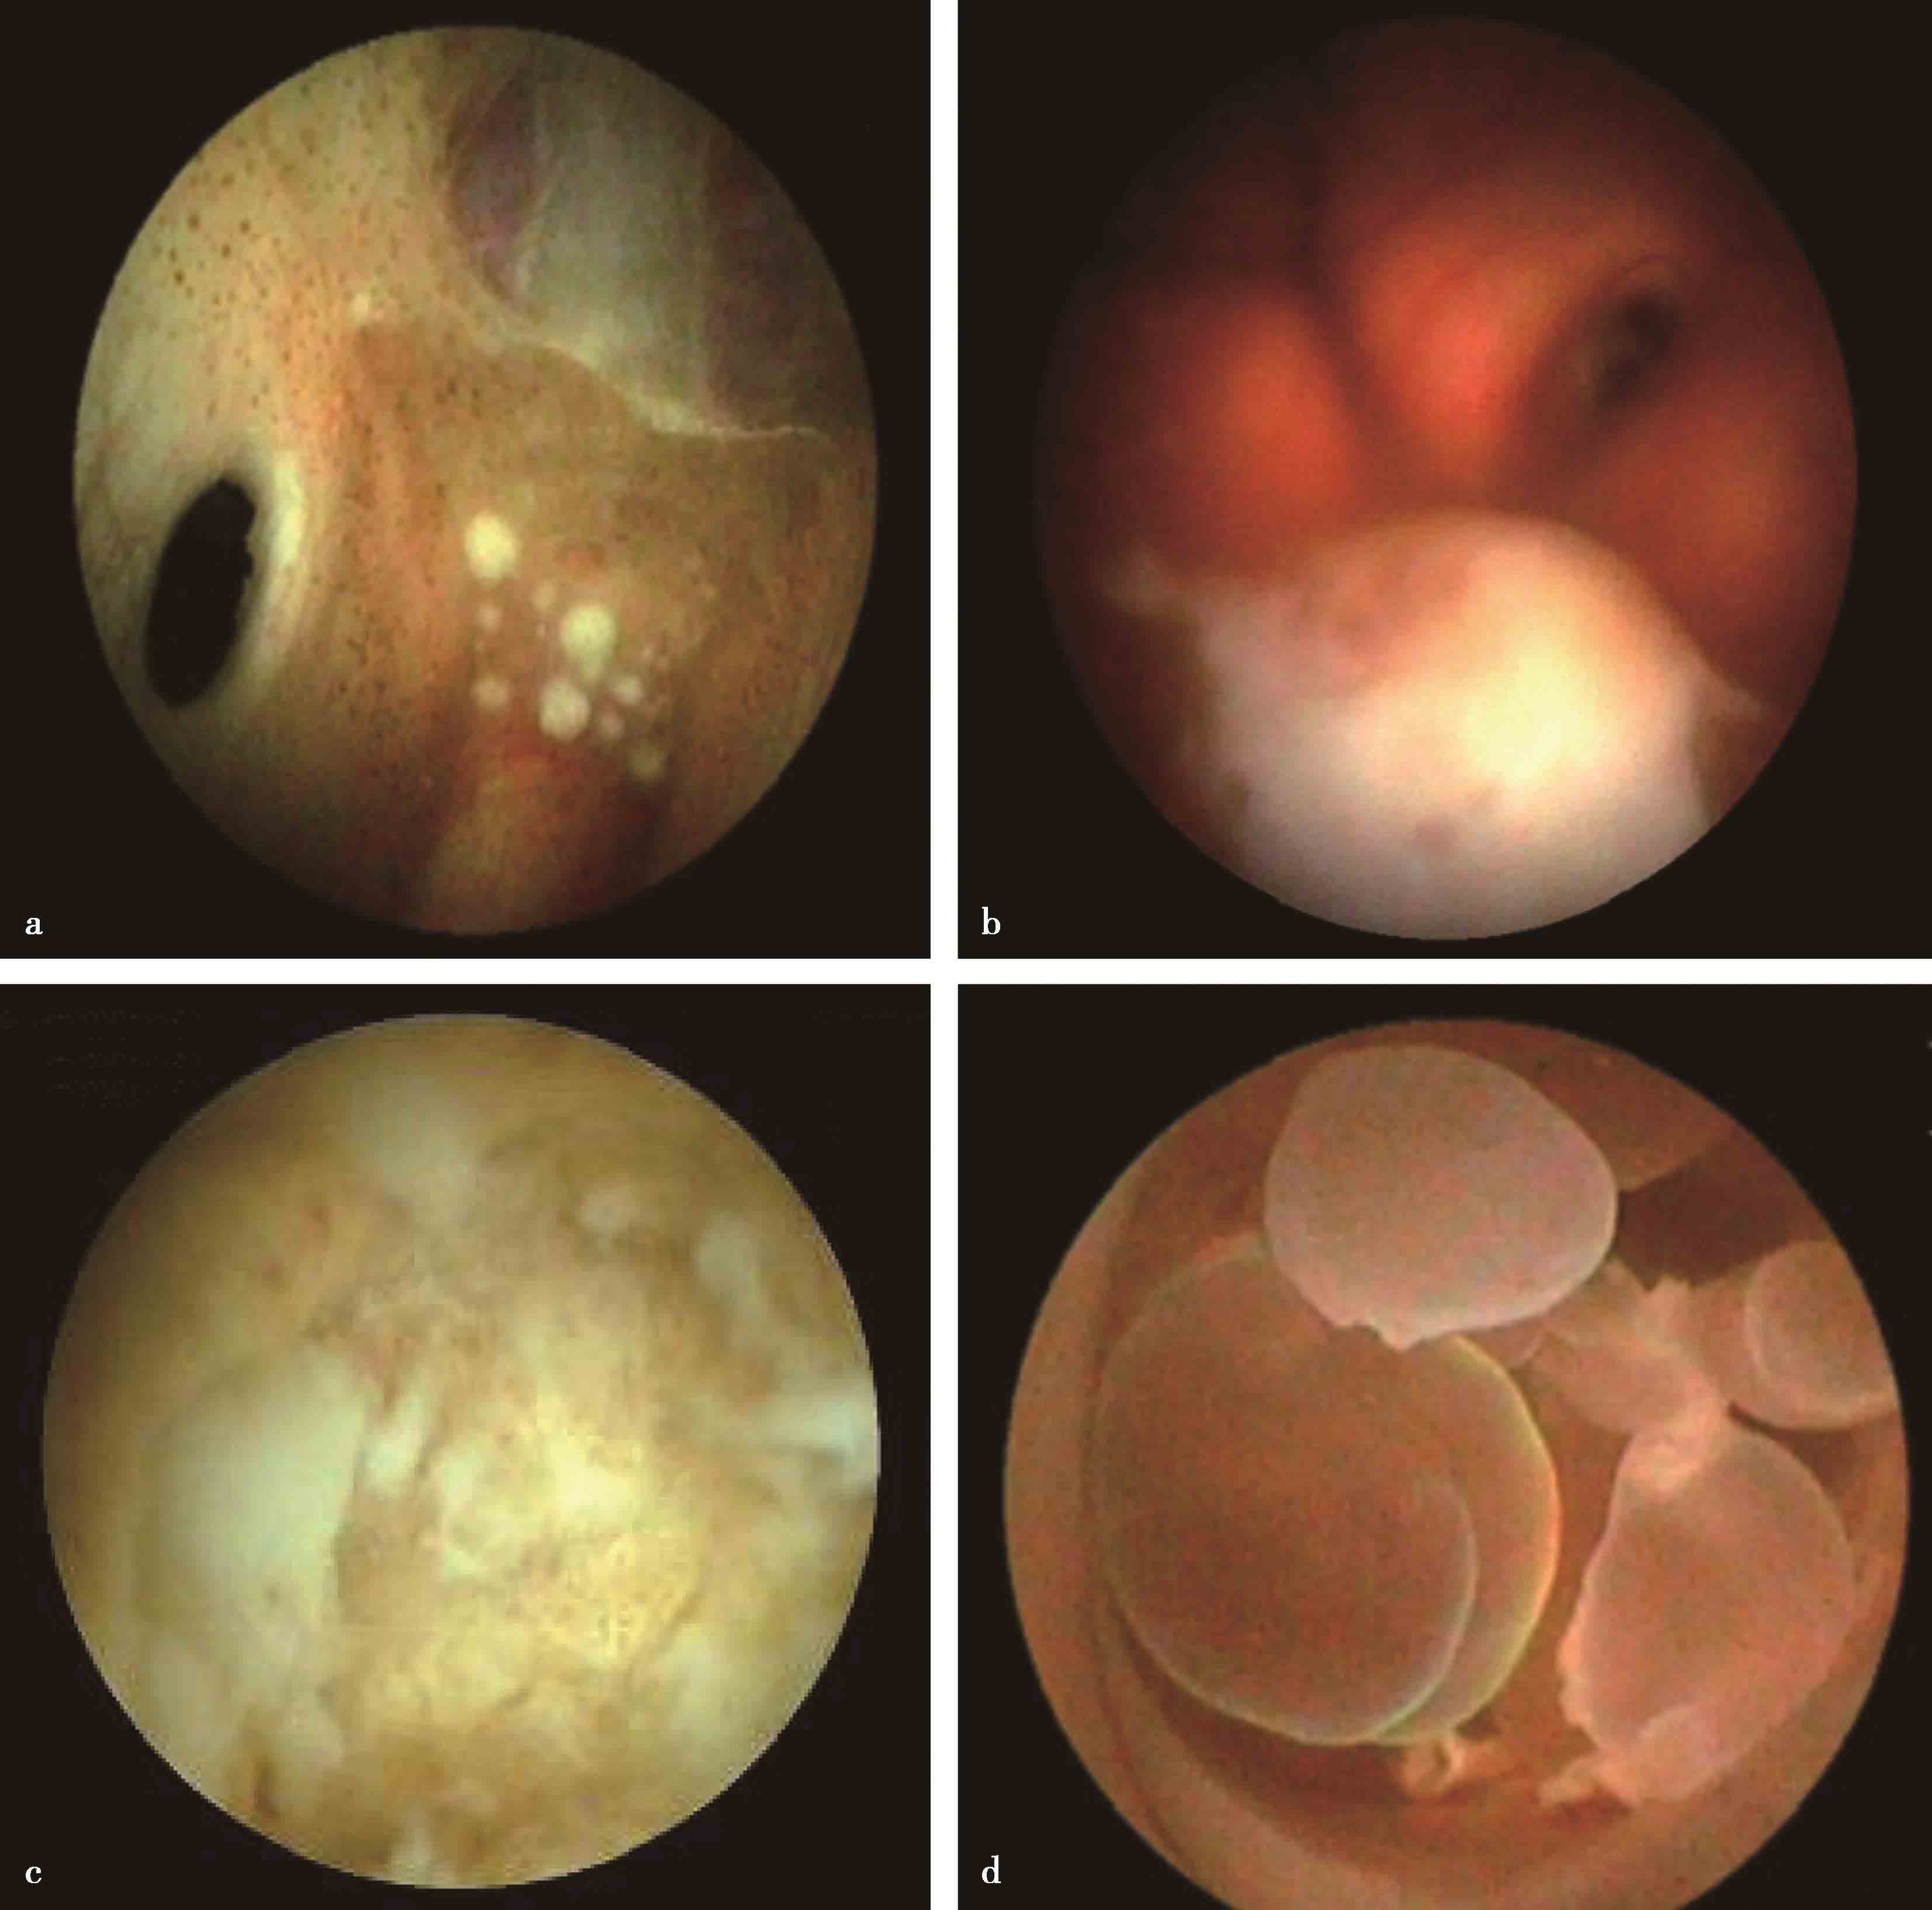

图3-1-1-4 感染后脑积水内镜下探查所见

a.脑室壁上的菌斑;b.脑室内结核所致干酪样坏死物;c.脑室内真菌感染;d.第四脑室内囊虫